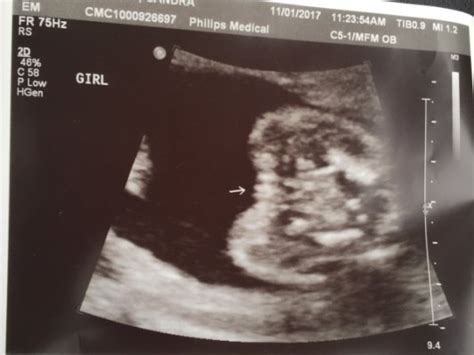

What Does Nt Mean On Dating Scan - Nuchal translucency (NT) ultrasound - BabyCenter Canada - This information will be provided for you at the time of your appointment.. 4 when a scan shows a nuchal translucency (nt) measurement of 3.5millimetres or more information for parents definitions nuchal translucency (nt) scan you will have an nt scan when you are between 11 weeks and 2 days and 14 weeks and 1 day pregnant. This information will be provided for you at the time of your appointment. Nuchal translucency refers to the sonographic image showing the fluid accumulation behind the fetus' neck. A dating scan will be done so you know what your new due date (estimated date of delivery) is and when to rebook for your nt scan. There are established and strict criteria for the accurate measurement of the nuchal translucency.

The nuchal translucency measurement can be taken during the dating scan. You may be offered a dating scan between eight and 10 weeks. If your dates are too late: There are established and strict criteria for the accurate measurement of the nuchal translucency. Between 11 weeks and 14 weeks of pregnancy or when your baby measures between 45mm (1.8in) and 84mm (3.3in) all developing babies have some fluid at the back of their neck. The nuchal translucency measurement was 3.6mm. Nuchal translucency (nt) is a collection of fluid under the skin at the back of your baby's neck. For the combined screening test, it is imperative that you do a dating scan first.

If your baby is moving around a lot, or if you're overweight or obese, it can be more difficult for the sonographer to get a good view of your baby. The nuchal translucency measurement was 3.6mm. A sonographer, who is usually a radiographer or a midwife trained in ultrasound, will complete your scan. There are differences between screening and diagnostic testing. The report that the midwife gets with the scan gives you all the information you need did you read it with the midwife? I wouldn't take an early scan as read, as it's not your official dating scan anyway. does it get more accurate as you get more pregnant? I have a scan next week, on tuesday, and will decide then what the next step is. The nuchal translucency measurement can be taken during the dating scan. In case of one patient she tried to do nuchal translucency ultrasound with transabdominal approach but due to maternal body habitus and fetal position she also used transvaginal. This scan is carried out from 11 weeks to 13 weeks and six days. I had my 12 week scan today and baby is measuring 13+3weeks. If i wa 13 weeks at dating scan does this then mean baby only really 11 weeks old? This information will be provided for you at the time of your appointment.

It is important for the measurement to be done properly to ensure an accurate result. Nuchal translucency (nt) measurement nuchal translucensy (nt) is the clear space in the tissue of your developing baby's neck. How is a dating scan performed? Then he or she will locate the nuchal fold and measure its thickness on the screen. An increased nt measurement does not always mean the baby has a problem but it does increase the risk.

The nuchal translucency scan is done between 11 and 14 weeks of pregnancy. Regarding the actual dating of my pregnancy, the hospital has labeled me currently at 12 weeks based on the size of fetus at 6cm. This measurement can indicate a higher risk of genetic abnormalities, particularly down's syndrome. Nuchal translucency (nt) measurement nuchal translucensy (nt) is the clear space in the tissue of your developing baby's neck. What does the conception + 2 weeks mean? The nuchal scan (nt scan) is a screening done during an antenatal ultrasound to measure the amount of fluid at the base of your baby's neck. A sonographer will apply a transducer (wand) to the outside of your stomach to measure your baby from crown to rump and check that the fetal age is accurate. #18 moments, feb 17, 2012.